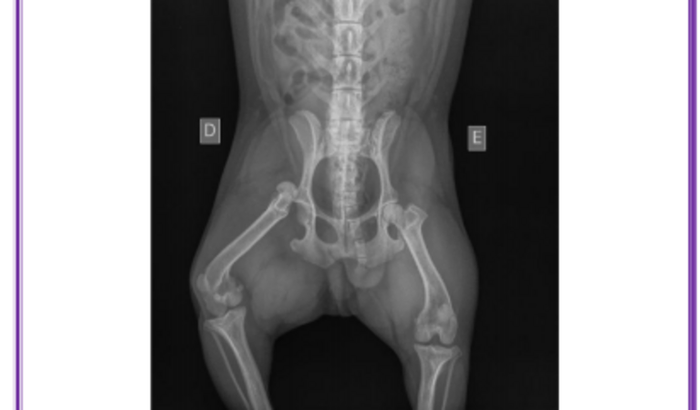

Cirurgia do Panqueca